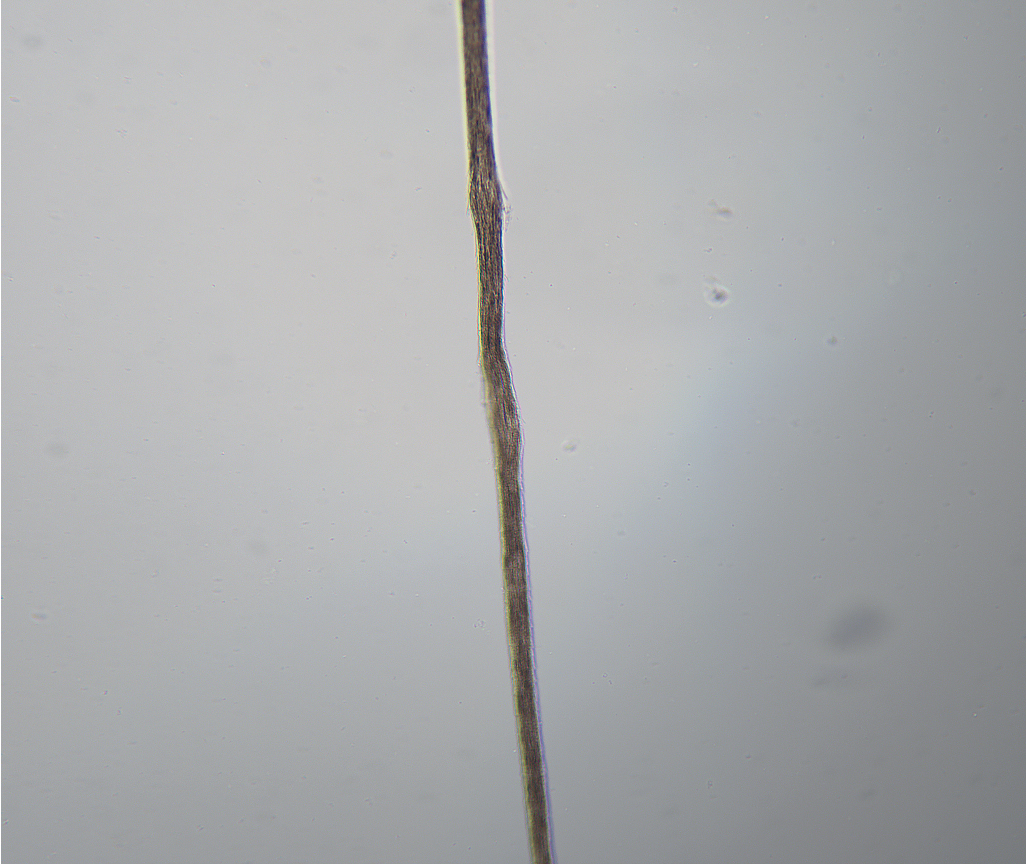

In addition to the general population seeking hair cosmetics for hygiene and to managing weathering, those with hair and scalp disease may also turn to the beauty industry for solutions. Patients with excessive sweat, oil, dirt, or hair product use may find regular hair and scalp hygiene especially helpful for follicular aesthetic appearance and prevention of the development of scalp diseases such as dandruff, seborrheic dermatitis, or folliculitis. Those with hair or scalp disease such as psoriasis, atopic dermatitis, dermatomyositis, or tinea may find that perfecting a hair and scalp hygiene routine along with personalized styling is important for overall disease management. Furthermore, cosmetic products are the foundation of treatment for those with hair breakage such as trichorrhexis nodosa and trichoptilosis ( Figs. 5.2 and 5.3 ).

Within the United States in 2021, routine hair and scalp hygiene and styling products were readily available and routinely used in the general population. However, a thorough understanding of hair cosmetics, styling, and processing requires individuals to also understand the concept of weathering. Weathering is a hair shaft process that results in hair damage from root to tip and includes decreased shine, elasticity, and, ultimately, breakage (level of evidence: 5) ( Pearl 5.1 ). , There are two types of weathering: natural and accelerated. In the process of natural weathering, the cuticle is worn away over time from hair brushing, combing, or other physical haircare maintenance techniques. Accelerated weathering includes damage to the hair’s cuticle and cortex proteins ( Fig. 5.1 ). , Those with long hair often demonstrate more severe weathering caused by repetitive injury of the hair shaft over time (level of evidence: 5). Processes that weaken hair fiber integrity and contribute to accelerated weathering include heat styling and chemical processing such as bleaching and permanent waving (level of evidence: 5). , Processes such as straightening, bleaching, and perming alter the protein structures of hair, causing irreversible damage (level of evidence: 5). , Other environmental factors in weathering include prolonged exposure to sunlight, resulting in loss of tensile strength, color changes, embrittlement, and split ends (level of evidence: 5). Sunlight exposure causes proteins and lipids to undergo degradation via a reaction between aromatic amino acid species and ultraviolet light, which produces reactive oxygen species such as hydrogen peroxide, hydroperoxides, and singlet oxygen. Overall, weathering of the hair fiber is expected over time in those with and without hair and scalp disease.